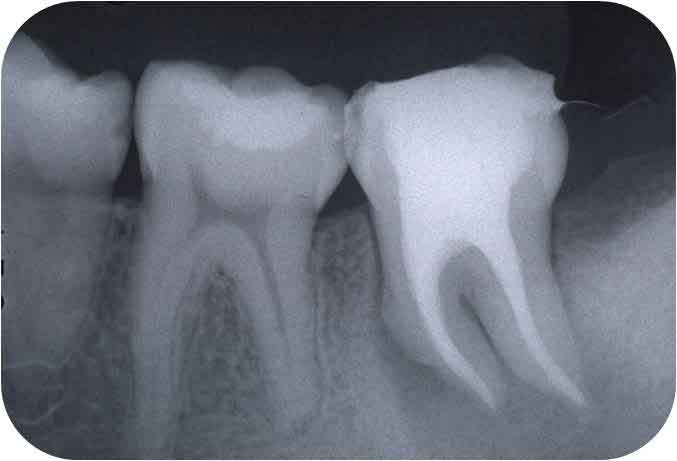

これが、根管が大きく(若年者であることが多い)、それも弯曲しているとなると、話がかわります。

根管が大きい=象牙質が薄い

という条件で、必要十分な拡大・形成を行い、歯根破折を起こさないようにできるだけ長く延命させていくということは、ストレートな根管であれば、慎重にファイルサイズを上げていくことで達成は可能だと思います。

一方、「ファイルサイズを上げる」 ということは 「ファイルのしなりがなくなる」 ということを意味するため、弯曲根管においては、通常の方法で治療を進めて行くに伴って、その弯曲部を無意識に、不用意につぶしていくことになります。

この結果、歯の脆弱化が進み、さらに抗原性の物質を取り残す可能性がある。

そこそこ細くて弯曲している根管より遙かに難しいのが、写真のような「太くて弯曲している根管」なのです。